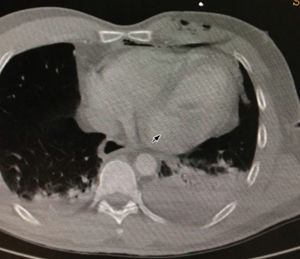

La tomografía inicial de tórax demostró hemotórax izquierdo importante (fig. 1)1. Se realizó ecocardiografía en la que no se encontraron signos de derrame pericárdico inicialmente, ni signos clínicos de inestabilidad.